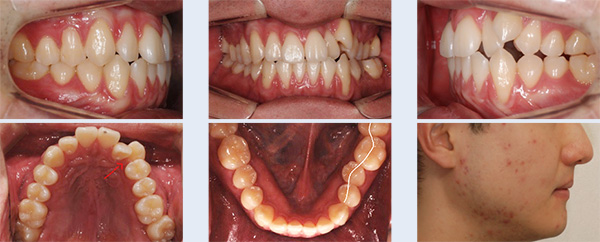

앞니 치열 불규칙하고 어금니가 잘 맞물리지 않아 소리가 나는 증상으로 내원한 22세 대학생입니다. 좌측 위 덧니가 관찰되었고 아래 어금니 배열이 바르지 않아 위 어금니와 정상적인 교합 관계를 보이지 않는 상태였습니다. 이를 빼지 않고 공간을 확보하기 위해 다음의 치료를 진행하였습니다.

① 위 치열을 측방으로 넓히기 위해 TPA(transpalatal arch, 횡구개호선) 사용

② 교정용 미니스크류(miniscrew)를 이용하여 사랑니가 있던 공간으로 위 어금니 후방 이동

③ 아래 치열 중간에 공간을 형성하기 위해 치간 삭제(interproximal stripping)

앞니 치열이 고르게 개선 되었으며 어금니가 자연스럽게 맞물리는 정상교합이 되었습니다. 자연치아를 빼지 않고 약간의 치간 삭제를 통해 교정 치료가 완료되어 환자 분의 만족도가 높은 케이스였습니다.